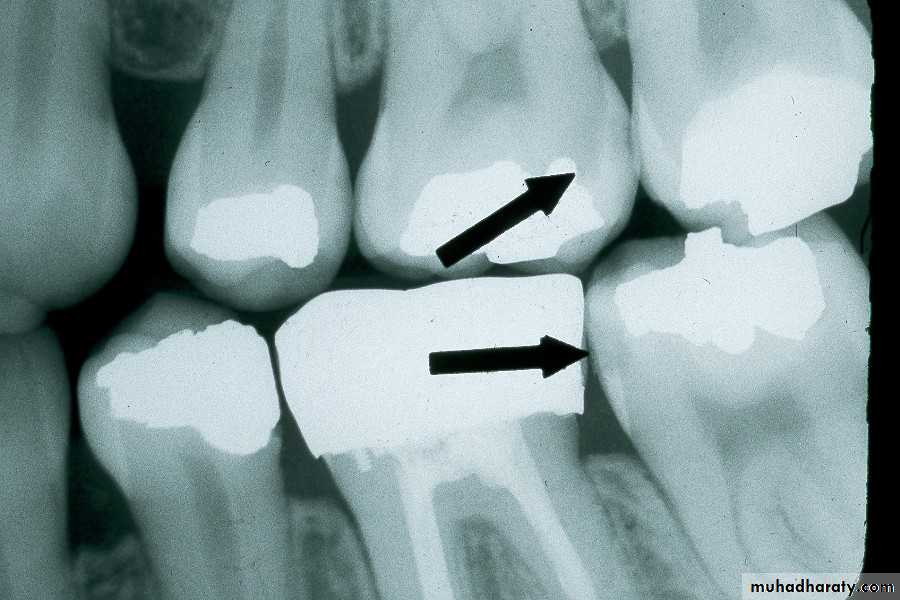

Interproximal Caries (Advanced)

extends to or through the DEJ and into dentin but does not extend through dentin more than half the distance toward the pulpAdvanced Interproximal Caries

An advanced carious lesion, which extends through the dentino-enamel junction (DEJ) and into dentin, seen on the distal surface of the mandibular first molar.

Advanced Interproximal Caries

Advanced lesion identified by arrows.